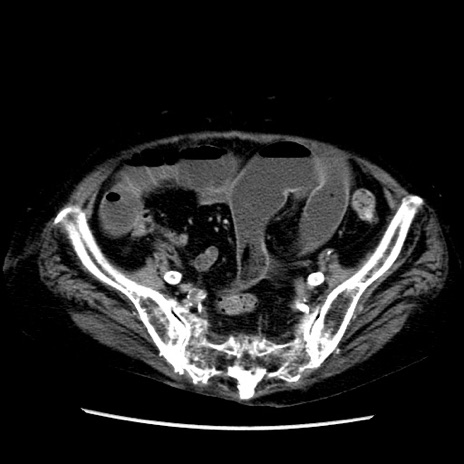

症例14(横断像)

【症例】 90歳代女性

【主訴】 腹痛・嘔吐

【現病歴】今朝から左側腹部痛を認めた。 経過観察していたが、嘔吐を認めたため来院。

【既往歴】 子宮癌術後

【身体所見】 意識清明、BP 127/54mmHg、P 98bpm Sp02 95%(RA)、BT 35.8°C、腹部平坦・軟腸ぜん動音聴取良好、右下腹部圧痛(+) 反跳痛なし

【データ】WBC 9800、CRP 0.46